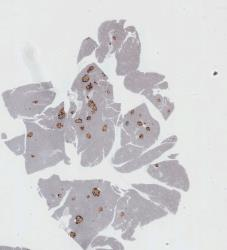

A. 常规细胞定量分析,其不限于某几种染色方法,如KI67,ER,PR,PAP,Bc1-2,HER2,EGFR等,特异染色的图像均可以进行分析;

B. 细胞核定量分析 包括阳性细胞/阴性细胞的区分检出,并针对阳性细胞进行强阳性、弱阳性的区分,得出更细致与精确的分析数据,如各类核数目,核面积,核比率等;

图7 表皮组织厚度分析 图8 胰岛素细胞检测分析